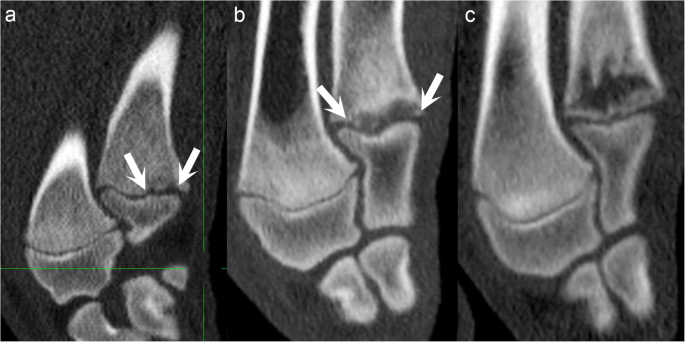

Multi-lobulated, stair-step lesions. Proximal is to the top and distal is to the bottom of each image. a Medial is to the left and lateral is to the right of the image. b Cranial is to the left and caudal is to the right of the image. a Pig 5, interval 1, left distal femur, frontal plane. There is a multi-lobulated lesion in the metaphyseal-side ossification front, consisting of four triangles close together (arrows) referred to as a stair-step lesion. b Pig 5, interval 1, left distal femur, sagittal plane. The lesion in a also contains three triangles close together in the sagittal plane (arrows)